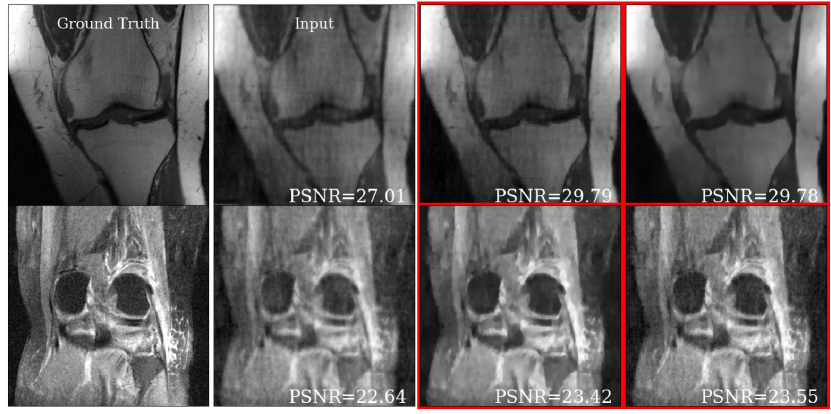

Figure 7: Representative slices for AO on CS-MRI task on 8-fold undersampled knees. Ground truth is denoted and two visually different but high-quality reconstructions (in terms of PSNR) are shown in red.

Fig. 7 shows representative brain and knee slices from the DHS HyperRecon-L model. The two corresponding reconstructions are selected as follows. First, we densely sample uniformly from [0,1]×[0,1]0101[0,1]\times[0,1] to generate 100×100100100100\times 100 reconstructions. Then, we filter out the reconstructions which are below some threshold PSNR value (we choose the 90th percentile). Finally, we choose the two reconstructions from this filtered set which are maximally separated by 2subscript2\ell_{2} distance.

We notice that the two reconstructions are significantly dissimilar despite the similarity in PSNR value. In the baseline setting, only one of these reconstructions would be available and finding another reconstruction would require training from scratch. With our model, users can search over the entire space of possible reconstructions and choose the one(s) they prefer. This highlights the value of this model as a tool for the interactive selection of many diverse reconstructions for further use based on visual inspection.